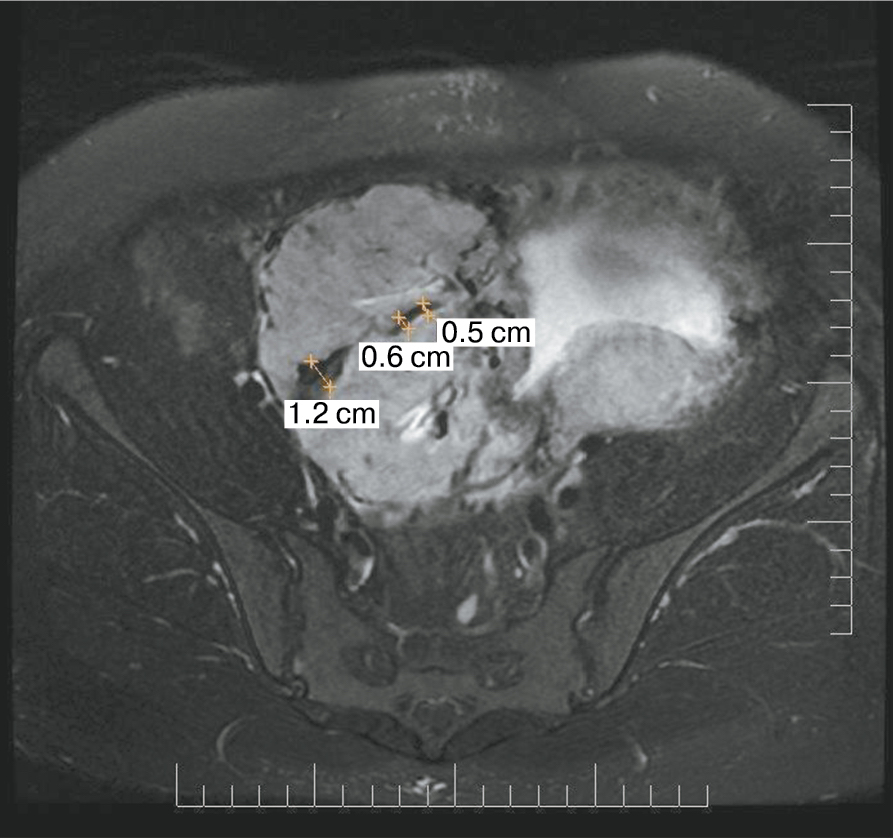

Согласно полученным данным, при сравнении в различных по глубине типах врастаний были установлены существенные различия в изменениях стенки мочевого пузыря (p=0,005, используемый метод: Хи-квадрат Пирсона). Наличие деформации контура стенки мочевого пузыря было выявлено в 85,7% случаев placenta percreta; однако признак также встречался и при менее глубокой инвазии тканей плаценты, не доходящей до стенки мочевого пузыря. Наличие деформации стенки мочевого пузыря и подозрения на экзофитные включения в просвете мочевого пузыря нередко дают ложноположительные результаты ввиду буллезного отека, обнаруживаемого на предоперационной цистоскопии, и расширения подслизистых сосудов.

Также стоит выделить особый тип плацентарной гиперваскуляризации, а именно включение в плацентарной ткани изменений по типу «обнаженного сосуда» (рис. 1, 2). Мы провели анализ встречаемости данного признака среди наших пациентов. Любопытным наблюдением явилось то, что данный симптом в нашей выборке встречался только при наличии placenta percreta – 6 случаев, а именно при поражении параметриев, и не встречался при плацентарной инвазии, ограниченной миометрием. «Мостовидные сосуды» были менее специфичны, тем не менее, их наличие также сопровождало тяжелые формы врастания, обусловленные более глубокой инвазией ворсин хориона, – 8 случаев.

Является ли симптом «обнаженного сосуда» патогномоничным для параметральной инвазии или нет, еще предстоит выяснить; однако в ходе исследования установлена его связь с частотой гистерэктомий в группах с наличием симптома «обнаженного сосуда», что, вероятно, обусловлено мощной сосудистой сетью коллатералей и неоангиогенезом. Во всех случаях обнаружения данного признака впоследствии была выполнена вынужденная гистерэктомия (рис. 3–6, пациентка Н., 37 лет).

Рис. 5. Корональная проекция МРТ. 1 – интрамуральная гиперваскуляризация; 2- измененный контур мочевого пузыря